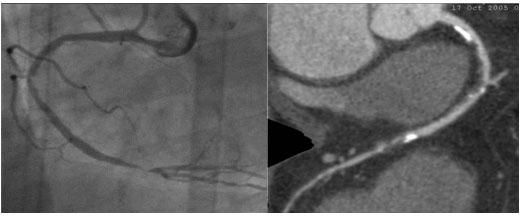

問:如何選擇冠脈CT檢查與冠脈血管造影檢查(DSA)?

答:64排螺旋CT冠脈成像屬于無創性檢查,排除冠心病的準确率達90%以上。該檢查假陰性率極低,換言之,若冠脈CT檢查正常,就沒必要再做冠脈造影。因爲冠脈CT爲疑似冠心病患者有效的篩查手段。

冠脈造影術屬于介入微創手術,其優勢在于可同時進行檢查與治療。符合急性冠脈綜合征、心肌梗死、不穩定型心絞痛患者,則應盡早進行介入幹預,直接作冠脈造影比較合适。